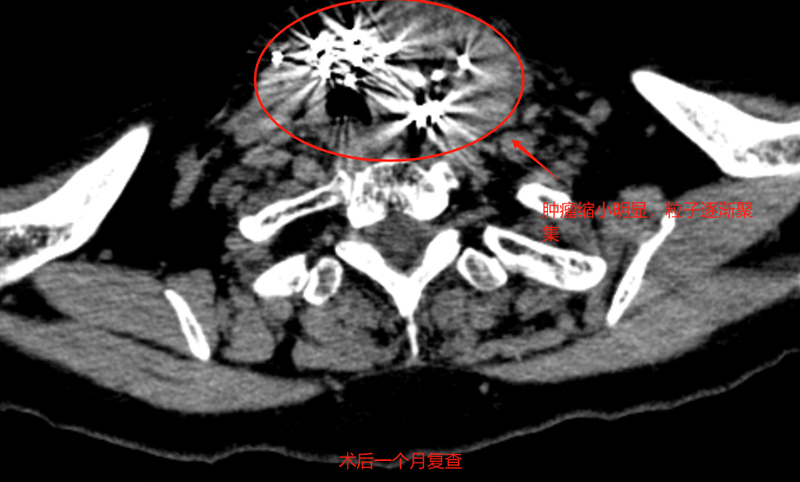

术后1月苑大娘回到我院复查,经过甲状腺CT增强所见:大小约4.0cm×5.6cm(前片5.0cm×6.3cm);余未见异常。粒子植入后肿物有明显的缩小!